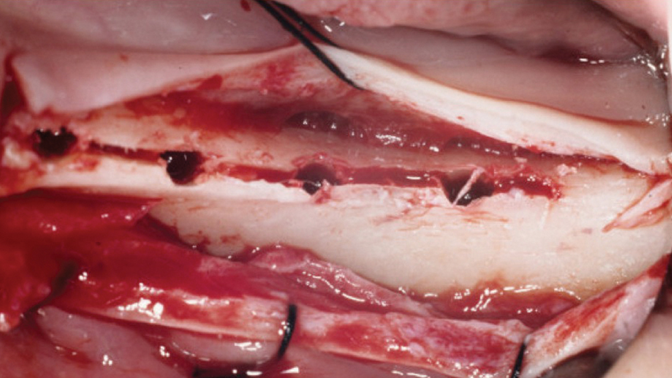

Clinical case: Installation of dental implants in complicated anatomic conditions using crest lifting methods

- Courtesy of Dr.Alexander Lysov, Russia -

Keywords

AnyRidge, complicated anatomic conditions, crest lift, MICA Kit, Dr. Alexander Lysov, bone regeneration, GBR, #26, maxillary posterior

Products:

AnyRidge implant system, MICA Kit